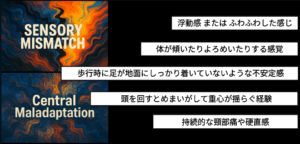

「歩くたびに床がずぶずぶと沈む感じがするんです」

「体がふわふわと浮いているようで、バランスが取れません」

「まるでお酒に酔ったようにふらついて、壁を掴んで歩かなければなりません」

めまい患者さんがよく訴える症状です。MRI、CTの検査では「異常なし」と診断されても、日常生活は依然として不安定な平衡感覚によって崩れていきます。一人での外出が怖くなり、人混みを避けるようになり、毎日繰り返されるめまいのために生活の活力を失っていきます。

視界がぼやけたりかすんだりしながらめまいがして浮動感、非現実感、離人症、ブレインフォグを特徴的に訴えるケースがしばしば見られます。

頭が重く圧迫感を感じたり、頭の中に何か詰まっている感じや押しつぶされるような感覚などの症状も訴え、ぼんやりした頭、めまい、頭痛、眼球の奥の痛みなどを伴うこともあります。ぼんやりした感じが続き、単語や記憶がうまく浮かばず、集中して何かをすることが難しく感じられます。本を読むことができず、普段楽しんでいた自転車運動や車の運転ができないほどだと話します。

回転性めまい(vertigo)、眩暈(dizziness)、平衡感覚異常を経験する多くの人々が、耳閉感、聴覚過敏、聴力低下、耳鳴りのような耳症状を伴っています。